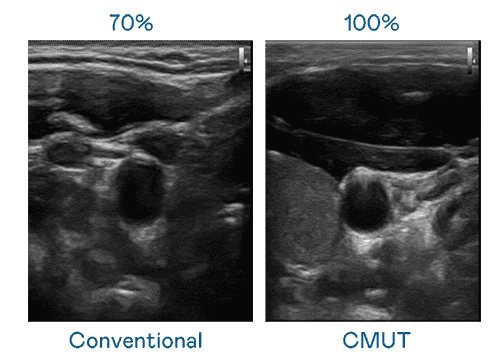

CMUT 技术是一种用电容式微机电元件来产生超音波讯号的技术。。。。与传统 PZT 压电式技术相比,,,CMUT 频宽增加 30%,,,更宽频的超音波讯号让影像解析度大幅提升,,,,是实现高影像品质医疗超音波扫描、、、、促进精准医疗发展的关键技术。。

大频宽带来超清晰影像

超音波影像的解析度高低,,,,首先取决于探头能发出的讯号频宽。。CG电子 CMUT 可提供高清晰的超音波讯号,,,,提供高频宽、、、、高灵敏度、、、、影像纹理细节更高的超音波影像,,,,协助医护人员缩短影像判读时间及利用精准的医疗影像进行诊断。。